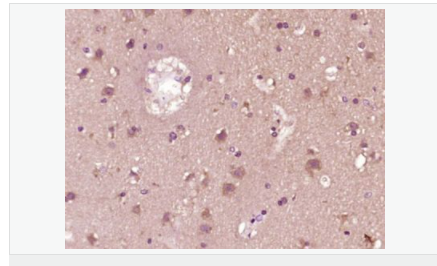

交叉反應(yīng):Human,Mouse,Rat(predicted:Pig,Cow,Horse) 推薦應(yīng)用:WB,IHC-P,ICC,ELISA

| 產(chǎn)品應(yīng)用 | WB=1:500-2000 ELISA=1:5000-10000 IHC-P=1:100-500 Flow-Cyt=1ug/test (石蠟切片需做抗原修復(fù)) not yet tested in other applications. optimal dilutions/concentrations should be determined by the end user. |